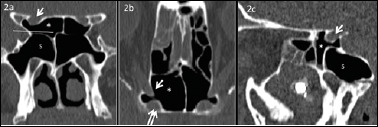

Abstract Image

Methods: In this study, 430 computed tomography scans of paranasal sinuses were analysed to establish the prevalence and different types of Onodi cells. Furthermore, the relationship between Onodi cell and different patterns of sphenoid sinus pneumatisation and surrounding structures were investigated. Special attention was paid to the relationship between Onodi cell and the optic nerve canal, particularly in cases when the optic nerve canal was bulging by more than 50% into the Onodi cell (Type IV).

Results: The Onodi cell was detected in 21.6% of cases, with the most common being Type I (48.5% right, 54.3% left). Type IV bulging of the optic nerve canal into the Onodi cell was observed in 47.1% of cases on the right side, 41.2% on the left side and bilateral in 11.7% of cases.